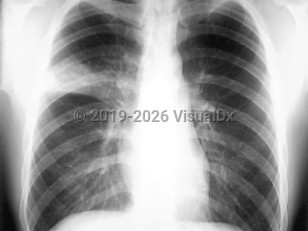

SARS can affect all age groups with a slight bias for females. There may be a prodromal illness consisting of fever, myalgias, headaches, and diarrhea. The respiratory phase starts 2-7 days after the prodrome with a dry cough and mild dyspnea. The spectrum of the illness can vary from a mild variant to a rapid and severe respiratory decline with hypoxia and features of acute respiratory distress syndrome (ARDS). Among hospitalized patients, 10%-20% eventually require mechanical ventilatory support. The physical examination findings may be mild and disproportionate to the chest x-ray (CXR) findings. A petechial rash may be seen. Peripheral blood lymphocytopenia and thrombocytopenia are common. The liver enzymes, creatine kinase, and serum lactate dehydrogenase levels can be elevated. There may be signs of disseminated intravascular coagulation. Acute renal failure has been reported.